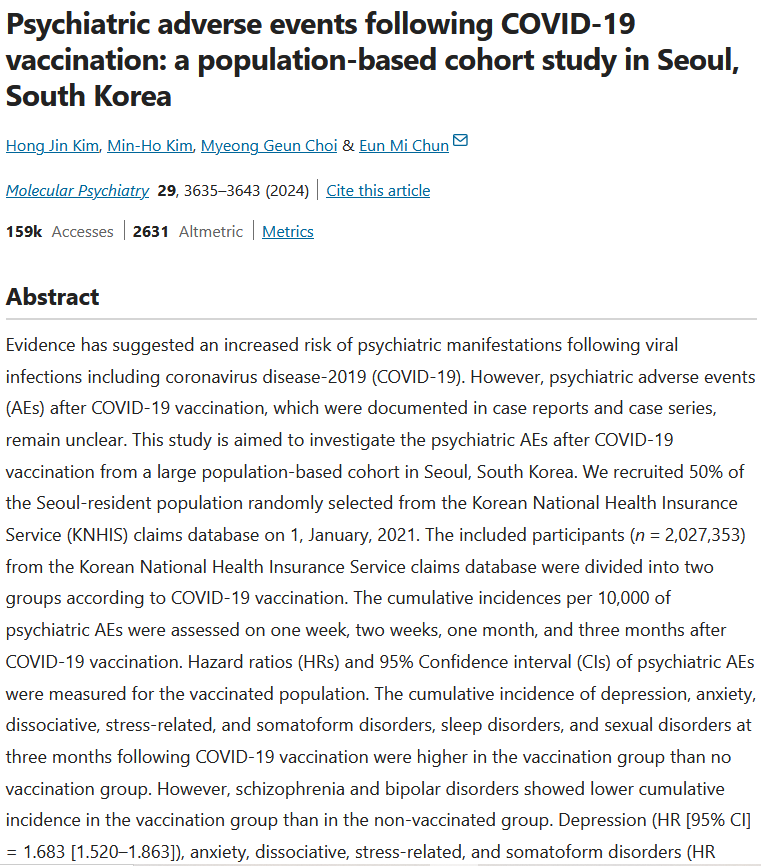

Τα εμβόλια κατά Covid-19 αποδείχθηκε ότι προκαλούν σε αρκετές περιπτώσεις νευρολογικές, αιματολογικές και καρδιακές παθήσεις στη μεγαλύτερη παγκόσμια μελέτη ασφάλειας εμβολίων έως σήμερα.

Περισσότερες από 13,5 δισεκατομμύρια δόσεις εμβολίων Covid έχουν χορηγηθεί παγκοσμίως τα τελευταία τρία χρόνια, όπως αποκάλυψε το Global Vaccine Data Network, σε έρευνα 99 εκατομμυρίων εμβολιασμένων ατόμων σε οκτώ χώρες, με στόχο τον εντοπισμό υψηλότερων του αναμενομένου κρουσμάτων μετά από εμβολιασμό για τον Covid, σε πολλές περιπτώσεις αυτά ήταν φονικά.

Η μυοκαρδίτιδα, ή φλεγμονή του καρδιακού μυός, εντοπίστηκε σταθερά μετά από μια πρώτη, δεύτερη και τρίτη δόση εμβολίων mRNA, σύμφωνα με τη μελέτη.

Η υψηλότερη αύξηση στην αναλογία παρατηρούμενου προς το αναμενόμενο παρατηρήθηκε μετά από δεύτερη δόση με το Moderna.

Η πρώτη και η τέταρτη δόση του ίδιου εμβολίου συνδέθηκαν επίσης με αύξηση κινδύνου της περικαρδίτιδας.

Οι ερευνητές βρήκαν μια στατιστικά σημαντική αύξηση των περιπτώσεων του συνδρόμου Guillain-Barre εντός 42 ημερών από μια αρχική δόση του εμβολίου ChAdOx1 ή «Vaxzevria» που αναπτύχθηκε στην Οξφόρδη – κάτι που δεν παρατηρήθηκε με εμβόλια mRNA.

Το ChAdOx1 συνδέθηκε με τριπλάσια αύξηση της θρόμβωσης του εγκεφαλικού φλεβικού κόλπου, ενός τύπου θρόμβου αίματος στον εγκέφαλο, που εντοπίστηκε σε 69 συμβάντα, ενώ θα ανέμενε κανείς μόνο 21.

Η μυοκαρδίτιδα συνδέθηκε επίσης με μια τρίτη δόση ChAdOx1 σε ορισμένους, αλλά όχι όλους, πληθυσμούς που μελετήθηκαν.

Παρατηρήθηκαν περιπτώσεις οξείας διάχυτης εγκεφαλομυελίτιδας μετά από εμβολιασμό με το εμβόλιο Pfizer-BioNTech.

Οι ανεπιθύμητες ενέργειες ειδικού ενδιαφέροντος επιλέχθηκαν με βάση προκαθορισμένες συσχετίσεις με την ανοσοποίηση, όσα ήταν ήδη γνωστά για τις παθήσεις που σχετίζονται με το ανοσοποιητικό και την προκλινική έρευνα. Η συγκεκριμένη μελέτη δεν παρακολούθησε το σύνδρομο ορθοστατικής ταχυκαρδίας ή POTS, που ορισμένες άλλες έρευνες έχουν συνδέσει με τα εμβόλια Covid.